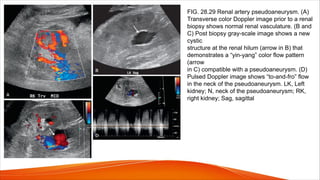

Pseudoaneurysms

• Pseudoaneurysms of the renal arteries are usually iatrogenic,

related to biopsy or arterial puncture, or represent sequela of

trauma or infection that results in disruption of the arterial wall.

• The blood that escapes the lumen is confined by the surrounding

soft tissues and hematoma.

• A saccular outpouching or cavity is usually seen extending from

the damaged vessel, and color.

• Doppler demonstrates swirling blood flow in the cavity during real-

time evaluation (“yin-yang” pattern)

FIG. 28.29 Renal artery pseudoaneurysm. (A)

Transverse color Doppler image prior to a renal

biopsy shows normal renal vasculature. (B and

C) Post biopsy gray-scale image shows a new

cystic

structure at the renal hilum (arrow in B) that

demonstrates a “yin-yang” color flow pattern

(arrow

in C) compatible with a pseudoaneurysm. (D)

Pulsed Doppler image shows “to-and-fro” flow

in the neck of the pseudoaneurysm. LK, Left

kidney; N, neck of the pseudoaneurysm; RK,

right kidney; Sag, sagittal